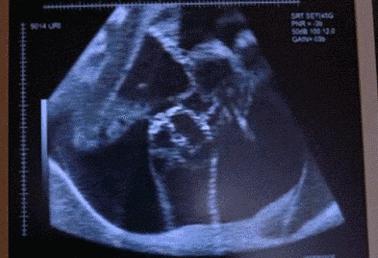

据台媒报道,台湾一名怀孕35周的产妇,在胎儿一阵狂踢后觉得腹部剧烈疼痛,超音波显示出现前置胎盘及羊水减少的现象,医院立即对该孕妇进行剖腹产。

在准备逢合子宫前,医生发现产妇子宫左上脚破了一个近8厘米的大洞,负责治疗的医生称该名产妇出现罕见的产科并发症:产前子宫破裂。原来,小女婴在妈妈子宫里练“武术”,导致妈妈的子宫被踢出一个洞,不但羊水漏光,还不断出血。